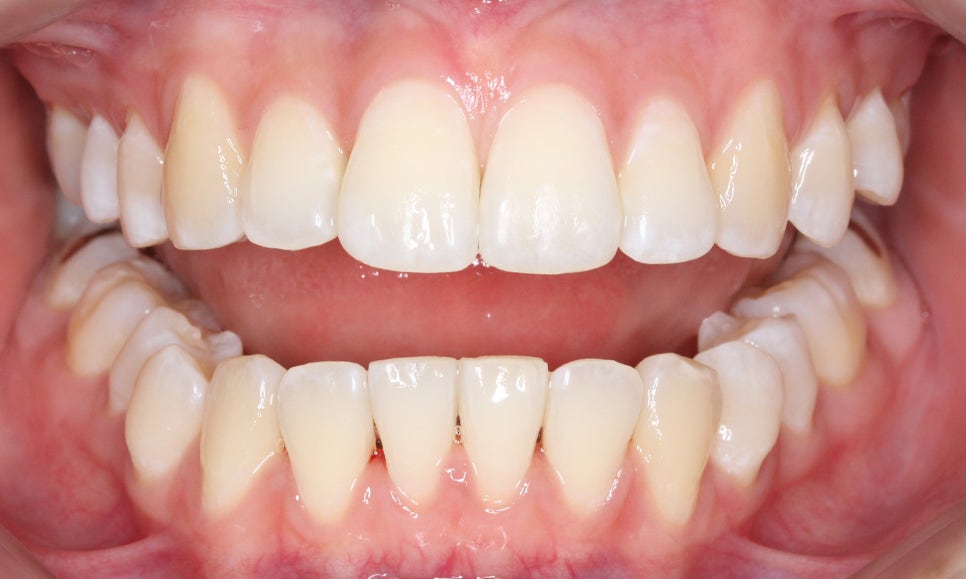

overbite 사진을 보면 상악 좌측 측절치가

하악보다 뒤쪽으로 교합되는 모습을

확인할 수 있는데요, 이렇듯 일부 치아에

반대교합 증상이 나타날 경우 2D교정이나

투명교정을 통해 단기간에 심미적인

치아 교정이 가능합니다.

전치부의 돌출 정도를 확인할 수 있는

overjet 수치는 비교적 돌출감이 없는 모습으로

거꾸로 물리는 측절치를 해결한다면

스마일라인의 심미성을 보완할 수 있을 것으로 보입니다.

좌우의 교합평면을 보면 구치부의 교합은

크게 틀어진 부분 없이 양호한 상태인데요,

상악의 경우 송곳니의 위치나 각도도

좋기 때문에 부분교정도 가능하나

전체적인 교합을 바르게 하기 위해

자가결찰브라켓인 클리피씨교정 장치를

적용하여 전체교정을 진행하였습니다.

상악의 경우 설측으로 뻐드러져 있는

측절치의 바른 교정이 중요한 포인트이기 때문에

이를 중심으로 교정 계획을 수립하였습니다.

또한 미세하게 발견되고 있는 crowding으로 인해

삐뚤어진 정중선 역시 바른 각도로 교정하도록 하였습니다.

하악은 상악에 비해 심하게 틀어지진 않았지만

전치부의 치아들이 회전된 모습이 나타나기 때문에

이를 바르게 교정하여 전치부의 심미성을

보완하도록 하였습니다.